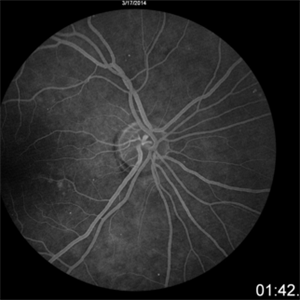

Radiation Retinopathy

Mar 12 2016 by David Callanan, MD

55-year-old with background diabetic retinopathy that developed renal cell carcinoma. Underwent radiation to left orbit. Extensive capillary dropout OS.

Condition/keywords: radiation maculopathy